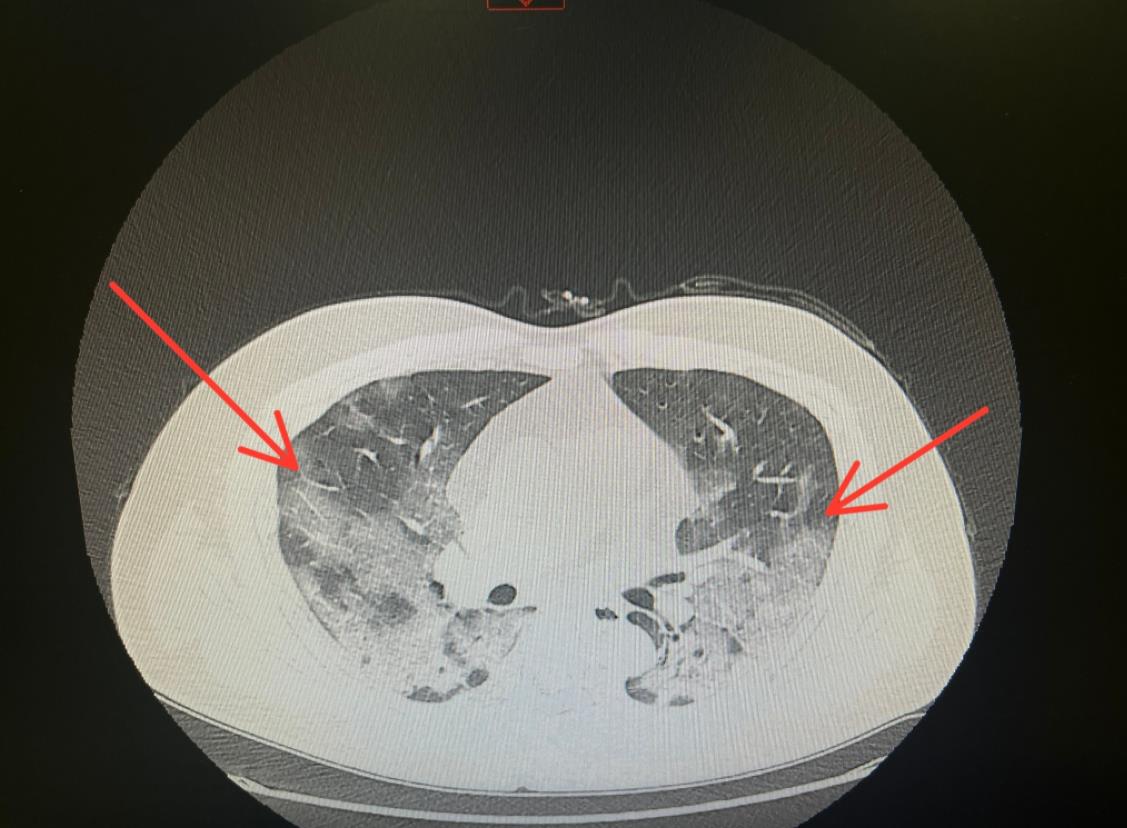

普通民众感染后如何判断是否存在肺部感染?2022年12月29日,在2022凤凰网财经峰会上,著名流行病专家曾光表示,可以通过血氧指甲仪,指标大于95都是正常的,93是一个界限,如果低于93,甚至低于90,就是重症的体现了。如果没有血氧指甲仪,可以通过呼吸次数判断,危重病人每分钟的呼吸次数可以超过30次,自身每分钟呼吸次数超过20次就要关注了。出现呼吸急促症状时要及时就医,不要等到太严重才采取行动。

很多人咳嗽不止,会担心会不会引发肺炎。实际上,咳嗽本身不会引起肺炎。当病毒细菌等病原体仅累及上呼吸道时,通常就会出现咳嗽;当炎症累及下呼吸道,就可能发展成为肺炎。如果出现以下5个症状,提示可能出现了肺部感染: